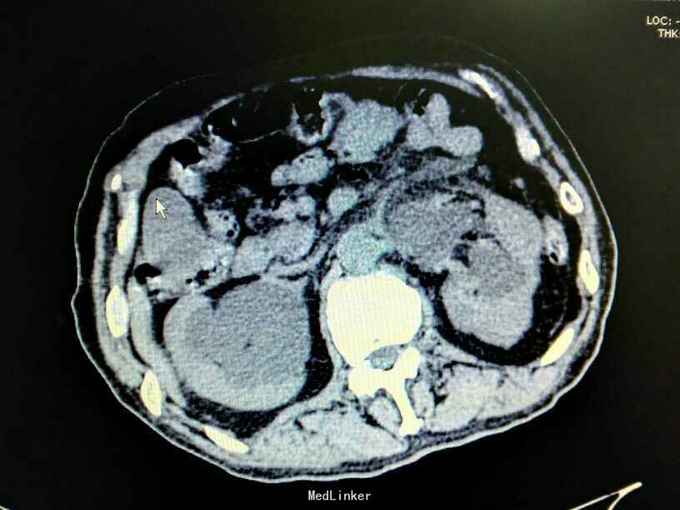

男性,87岁,进行性排尿困难10年,小便不能自解2天入院。无血尿,无发热、腰痛。一直口服藏药治疗前列腺增生症。既往无高血压、糖尿病。

腹部明显膨隆。耻骨上膀胱区扣浊。肾区无扣痛。尿常规少许白细胞。肌酐506,电解质正常。Hb116。

前列腺增生症 尿潴留 双肾积水 肾功能不全,膀胱结石,尿路感染,双肾多发囊肿。给予留置导尿,间断分次放尿后,出现肉眼血尿,持续膀胱冲洗,颜色较红,伴血凝块间断堵管。